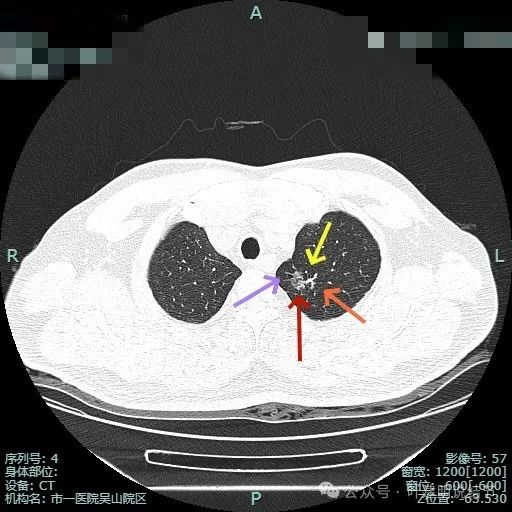

先看非薄层影像:

明显分叶以及血管贴边并有异常增粗。

边缘毛刺,血管进入,灶边有细支气管扩张,整体轮廓与边界清。

血管异常增粗进入,灶内小空泡征,表面不平有浅分叶,灶内密度感觉欠均匀。

1、主病灶诊断问题:左上主病灶混合密度,表面不平,灶内显得杂乱;有血管异常增粗进入与穿行;边缘不平毛糙伴细毛刺征;灶内小空泡,灶边细支气管扩张;月牙铲征可见。诸多影像特征都指向其为浸润性腺癌可能性大,至少是微浸润性腺癌。而且随访长达5年余,所以不考虑炎性病变。由于密度不纯,血管进入与异常增粗,存在一定风险,不宜过度随访。加上位置仍不算太中央,能局部楔形切除,创伤小、恢复快,我们倾向手术切除。